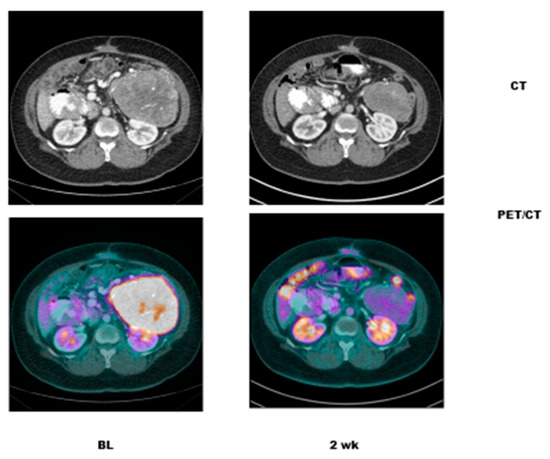

- Case # 2:

- This is an 82 year old female with gastro-intestinal stromal tumor (GIST). Baseline FDG/PET study was performed off tyrosine kinase inhibitor therapy and she was initiated on a therapy. Repeat study was performed two weeks after initiation of Gleevec® (Imatinib) a specific c-KIT inhibitor. Both anatomic and metabolic response was seen. Although there was still a residual anatomic abnormality, the tumor had complete metabolic response. This illustrates that the power of early functional imaging (Figure 3).